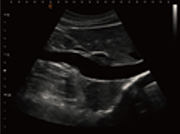

下腔静脉,B模式